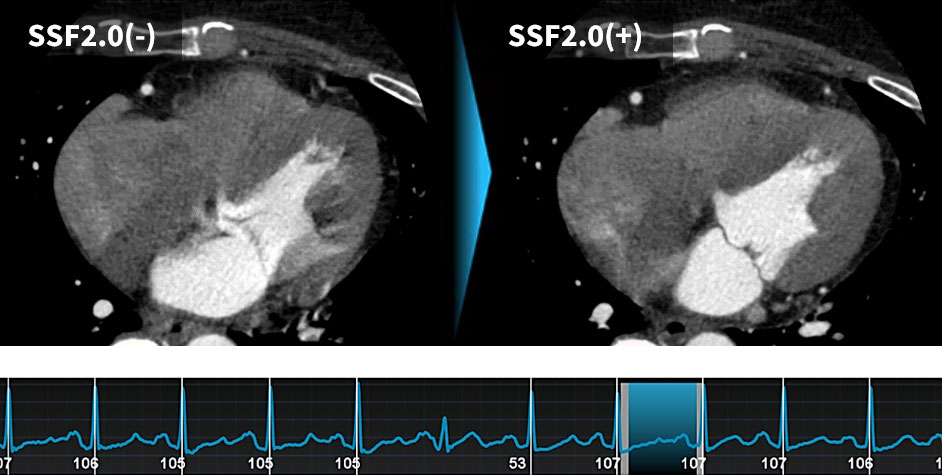

SnapShot Freeze2.0:

指定の心位相でモーション抑制画像を生成する機能。

心構造を含め高精度な静止画像を得られるため、治療プランニングにも有用な画像を提供できる。

GEHC CTには心臓撮影後のモーション抑制技術として、動態ベクトル解析を用いたモーション抑制アルゴリズム「SnapShot Freeze 2.0」(以下SSF2.0)があります。SSF2.0では、ターゲット心位相とその前後の心位相、合計3つの心位相のデータを用いて、心臓を構成する各ボクセルの動態を3次元的にベクトル解析し、変化量をフィードバックして静止画像を生成します。これに0.23秒ローテーションを組み合わせることで、より高精度な静止画像が取得可能となりました。

当院では、心拍に依存せず、多くの症例でβブロッカーを使用せずに撮影を行っています。その効果として患者様がCT室に滞在する時間が5分以上短縮することができています。また、以前のCTでは、モーションアーチファクトにより評価が困難である症例では、しばしばCAGによる精査が必要でしたが、0.23秒ローテーションとの併用により、ほぼすべての症例でモーションアーチファクトがない画像が得られ、不必要なCAGを減少させることができました(図6、7)。

RevolutionApexElite_Minaminojunkanki08.jpg

(図6)

・平均心拍数107bpm、不整脈(+)、息止め困難の症例

SSF2.0処理を施した結果、

冠動脈および心筋のモーションアーチファクトが補正された。